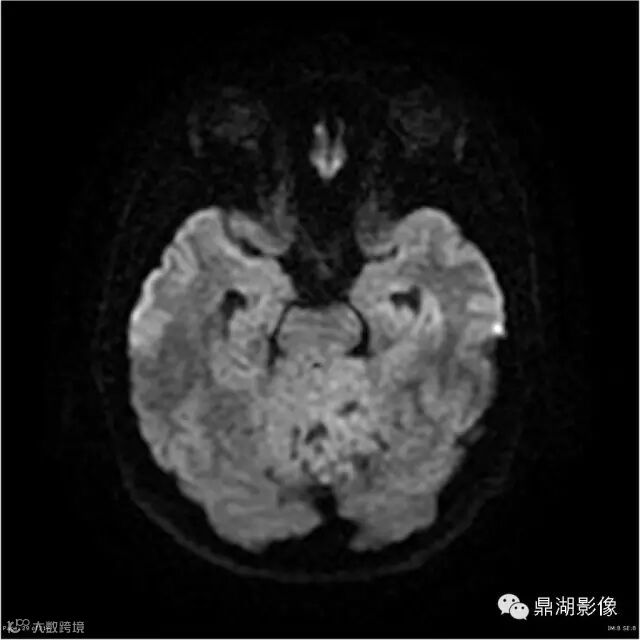

Axial DWI

本例为一例实质性血管母细胞瘤。实性血管母细胞瘤CT平扫示病灶呈等或高密度,增强后可见明显强化。MRI平扫通常病灶很不均质,T1呈稍低信号为主的较混杂信号,T2呈等、高信号,DWI通常呈低信号或等信号。文献报道,实性血管母细胞瘤较典型的表现为瘤内及瘤周扩张的流空血管影,瘤周中、重度水肿。因此,小脑半球区的单发肿块伴流空血管影,周围大片水肿以及增强后肿块明显强化"形态规则"边界清楚,此时应将实性血管母细胞瘤考虑在内。

实性血管母细胞瘤须与脑膜瘤、淋巴瘤、室管膜瘤等鉴别;脑膜瘤,为脑外肿瘤,极少发生囊变,多数可见“脑膜尾征”,出血及坏死少见,瘤周水肿较轻;淋巴瘤,常位于深部脑组织,无血管流空影,DWI上呈高信号,文献报道,实性血管母细胞瘤 DWI( b=1000) 呈低信号有助于两者鉴别;室管膜瘤一般瘤周无蚓状流空的肿瘤供血动脉,增强时强化程度不及血管母细胞瘤。